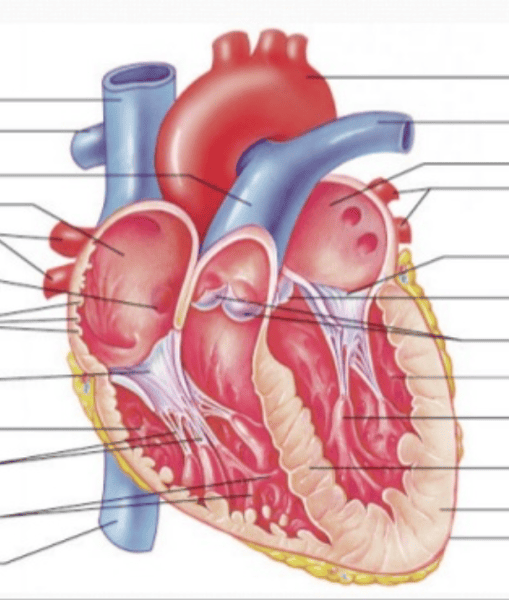

Gross Anatomy of the Heart

Left ventricle and atrium

Right ventricle and atrium

Artery

Vein